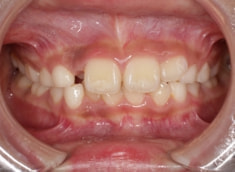

治療前